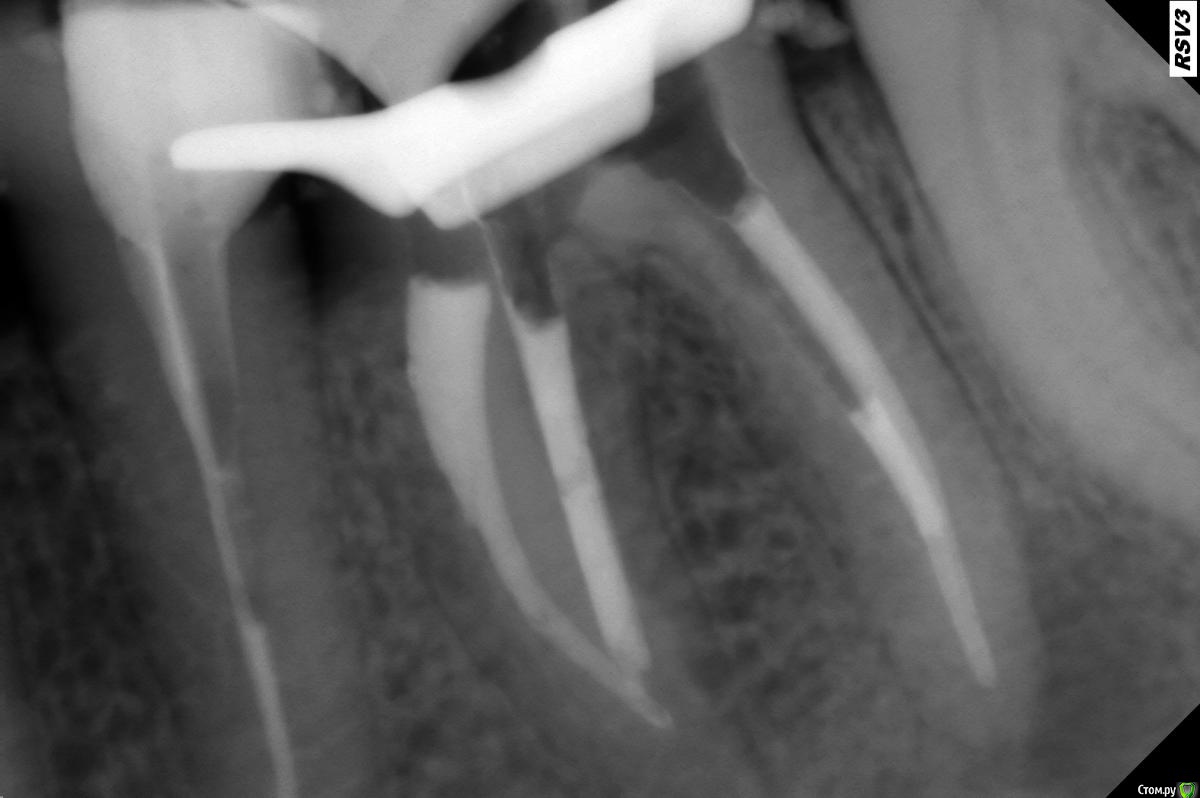

ceti Опубликовано 23 июля, 2015 Поделиться Опубликовано 23 июля, 2015 Здравствуйте, уважаемые специалисты Проконсультируйте пожалуйста. Зуб 36 был депульпирован лет 20 назад, установлены металлические штифты. Примерно 7-8 лет назад металлические штифты заменили на стекловолоконные. Полгода назад на КТ был обнаружен воспалительный процесс у верхушки дистального корня. Фрагмент томограммы: Доктор предложил перечить каналы еще раз, под микроскопом и более качественно. Каналы перелечили, но, как я понимаю, до конца их пройти не удалось: Прошу совета, что дальше делать. Можно ли рассчитывать на положительный эффект по результатам перепломбировки, или стоит попробовать перелечить каналы еще раз? В зубе (дно пульповой камеры, если не ошибаюсь) есть небольшая трещинка, но по словам доктора она не уходит в корень. Не знаю видно ли ее здесь, на всякий случай фотография: https://drive.google.com/open?id=0BwAD98i97KuPUEtHSDhBNWJ5TnR5M25ZdGd3d05HWnRmQWVj Также, в процессе лечения возникли болевые ощущения, пришлось сделать анастезию. Позже доктор сообщил, что в одном из каналов сохранились остатки пульпы, но потемневшие, без крови. Это действительно могло быть причиной, из-за которой возникла боль? Заранее благодарю за помощь. Ссылка на комментарий

St. Опубликовано 24 июля, 2015 Поделиться Опубликовано 24 июля, 2015 Снимок после перелечивания выглядит прилично. Ещё раз лезть в каналы - надобности не вижу.Однако нужно будет сделать контрольные снимки через 6 и 12 мес. 1 Ссылка на комментарий